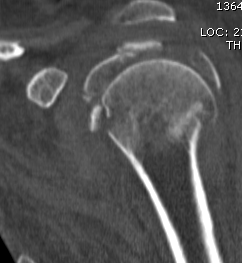

proximal humerus fracture Background ORIF with locking plate Arthroplasty Greater tuberosity fractures Lesser tuberosity fractures / avulsions Book traversal links for Proximal humerus fractures ‹ Pectoralis Major Tears Up Background ›